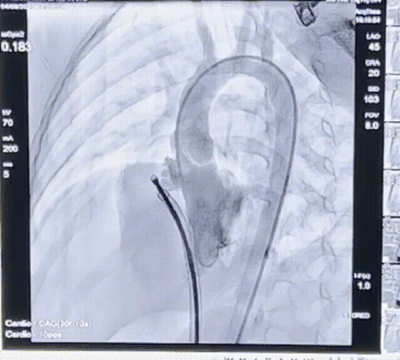

术后造影

术前超声

术中在造影指导下建立“股动脉-主动脉-左心室-室缺-右心室-右心房-下腔静脉-股静脉”轨道后,送入10 F鞘管,再经输送鞘送入一枚8 mm MemoSorb®全降解封堵器。随后在经胸超声指导下先释放左盘面,牵拉确定左盘面释放稳定后,继续释放右盘面,左右盘面释放后,锁紧成型线,MemoSorb®全降解封堵器完全成型,再次行经胸超声观察封堵器形态及封堵效果。经胸超声结果显示MemoSorb®全降解封堵器形态良好,封堵完全,无残余分流,遂完全释放封堵器,回收成型线。术后造影显示无残余分流,超声结果显示封堵结果十分理想,顺利完成手术。